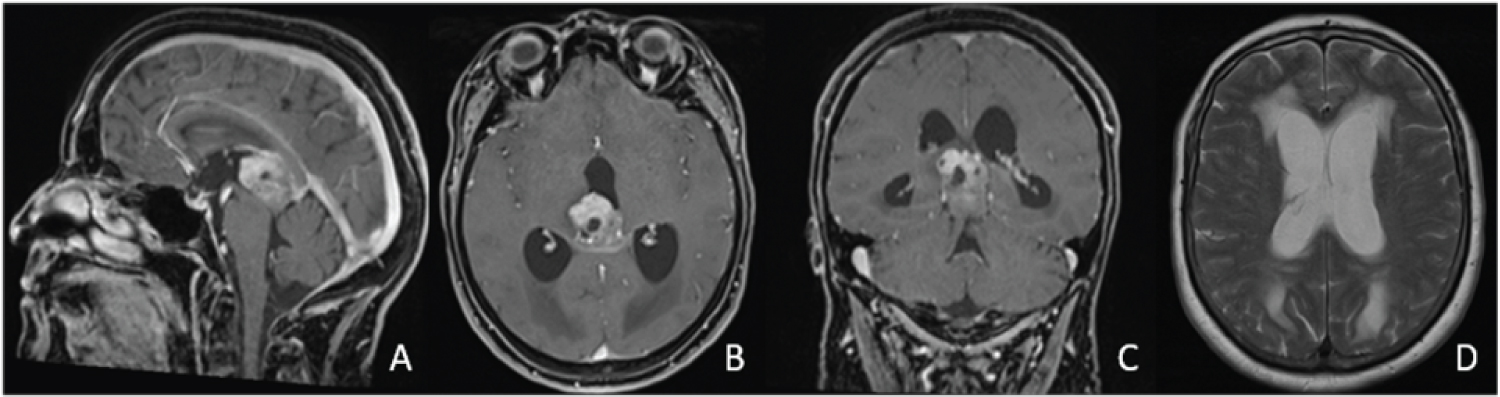

Figure 1: A,B,C) Inhomogeneously contrast-enhancing tumor predominantly located in the third ventricle with infiltration of splenium corporis callosum and obstruction of the aqueduct; D) Causing occlusive hydrocephalus. View Figure 1